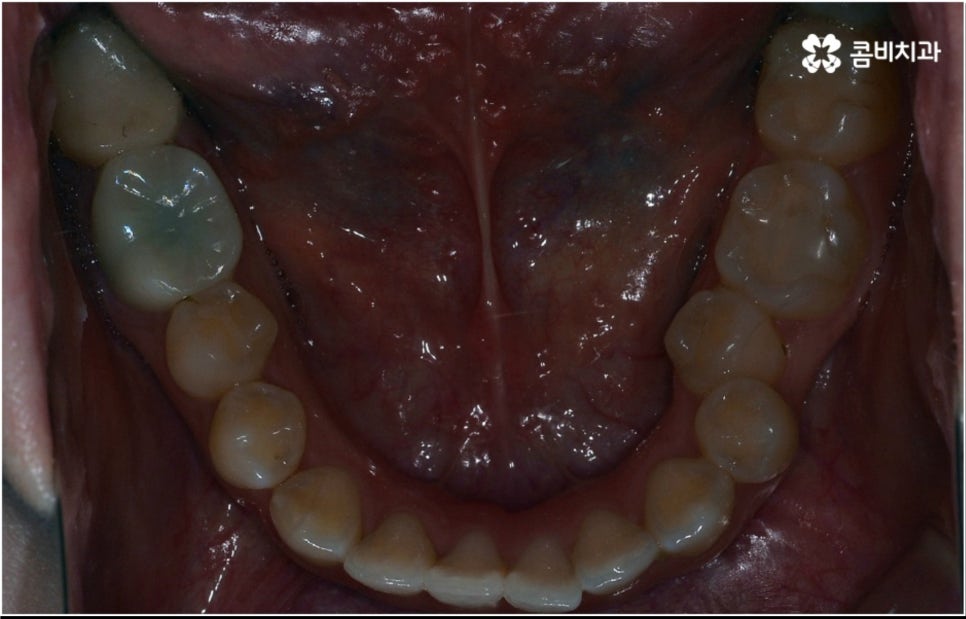

3D CT 등 정밀 검진 기계를 통해 꼼꼼하게 검진을 한 후 환자분들의 부정교합의 종류 및 정도 등에 따라 각자에게 맞는 교정 치료 계획을 수립하게 되는데, 내부 공간이 얼마나 있는지에 따라 발치가 필요한지 아닌지 여부도 달라지고 또 같은 부정교합이라고 해도 사람마다 잇몸 건강이나 치근 상태 등에 따라 잇몸뼈가 벌어지면서 치아가 이동하는 속도, 치아가 자리잡는 양상 등도 모두 달라지기 때문에 성인 치아교정 기간 총 소요 시간은 모두 달라질 수 밖에 없을 거예요.

치열이 삐뚤어져 있으면 기능적 심미적으로도 불편하지만 구강 건강과 관련하여 음식물 찌꺼기가 자주 끼고 충치 및 잇몸병과 같은 구강 질환에 노출될 가능성이 높아지는 등 관리가 어렵다는 문제도 커지기 때문에, 점점 길어지는 노년기에 건강하고 활기찬 생활을 하기 위해서 구강 건강이 굉장히 중요한 역할을 한다는 점을 상기해 봤을 때 중장년 성인 교정 치료에 대해서 괜한 두려움으로 미루기 보다는 더 늦기 전에 검진을 받아보고 필요한 도움을 받을 수 있는지 적극적으로 알아보는 것이 보다 바람직한 태도라고 할 수 있을 거예요.